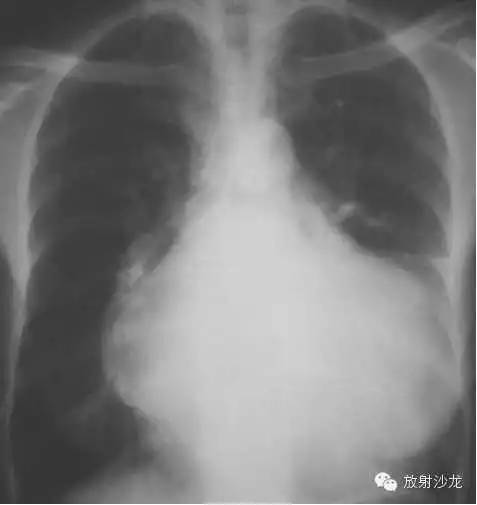

心包炎(pericarditis)

1、心脏向两侧增大,正常心缘弧度消失。

2、腔静脉增宽(体静脉回流右房受阻)。

3、心脏血管比率增大,主动脉影缩短。

4、心缘搏动下降,主动脉搏动正常。

5、肺纹理减少或正常(右心排血量减少)。

6、造影:各心腔无扩张,腔静脉扩张。